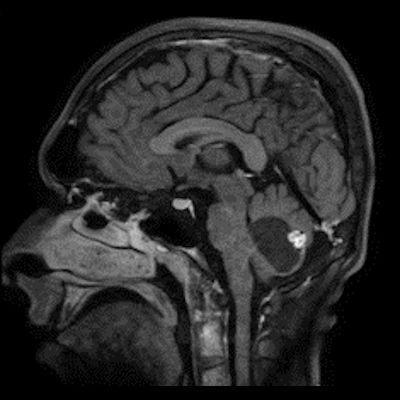

24 yaş, E

Baş ağrısı

4.ventrikül tabanına oturmuş posterior fossada hemanjioblastoma

Hemangioblastoma